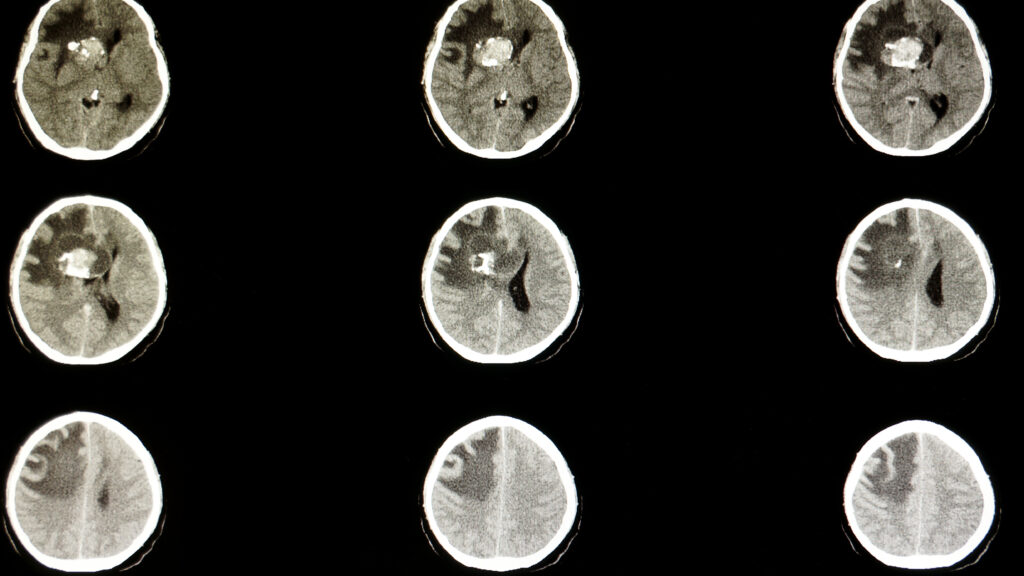

A couple married for more than 50 years has survived six cancer diagnoses between them. They emphasize the importance of personal knowledge of one's own body.